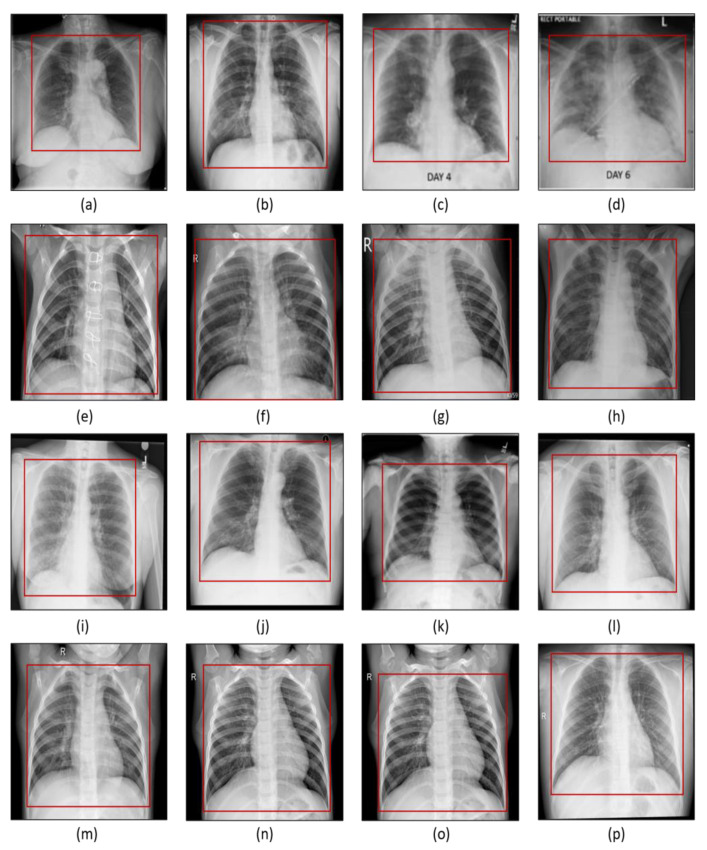

The data source and the details about the data are explained in this section. Four datasets were used which are discussed here. From each dataset, we chose 2500 images that were used in our research study. Figure 1 shows the examples of samples of each dataset used for this research work.

Figure 1.

(a–d) COVID-19 chest X-ray, (e–h) pneumonia chest X-ray, (i–l) lung opacity chest X-ray, (m–p) normal chest X-ray. The red box signifies the region of interest cropped from the original image for analysis.

In image preprocessing, the aim is to enhance the diminishing features of the image using different image processing techniques thus improving the quality of the image to be used for training the model. All the X-ray images used in this research study were cropped (Figure 1) and resized to extract the ROIs and have identical widths and heights before being fed to the learning algorithm. Moreover, a bias field correction technique is applied to correct the inhomogeneous intensity in the image.